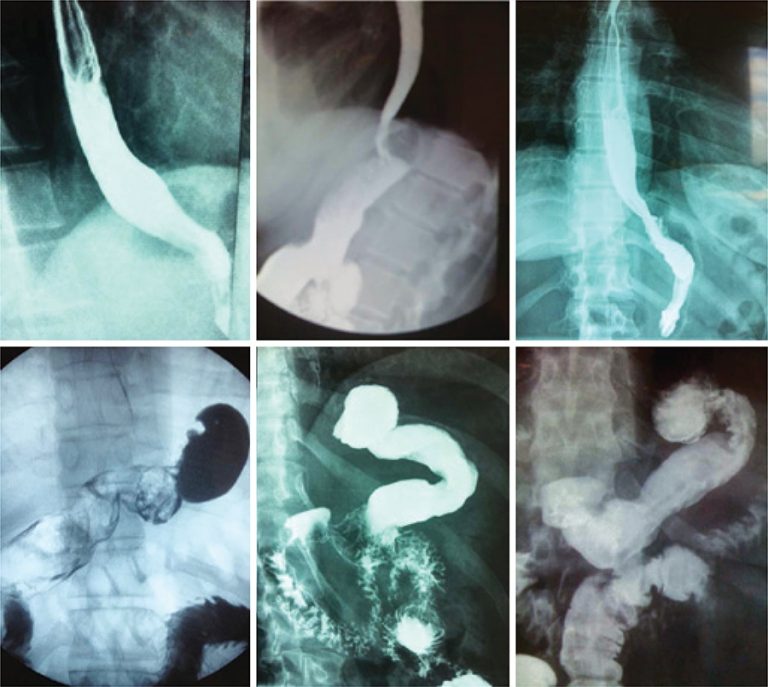

Objetivo A gastrectomia vertical é o procedimento cirúrgico para tratamento da obesidade que mais cresce em indicações. No entanto, esse procedimento pode causar ou agravar a doença do refluxo gastresofágico. Este artigo buscou descrever originalmente a adição de procedimentos antirrefluxo (remoção de coxins gordurosos do hiato, hiatoplastia, pequena plicatura e fixação do remanescente na posição anatômica), além de relatar seus resultados precoces e tardios. Métodos Foram submetidos à gastrectomia vertical com medidas antirrefluxo 88 oito pacientes obesos com sintomas de […]